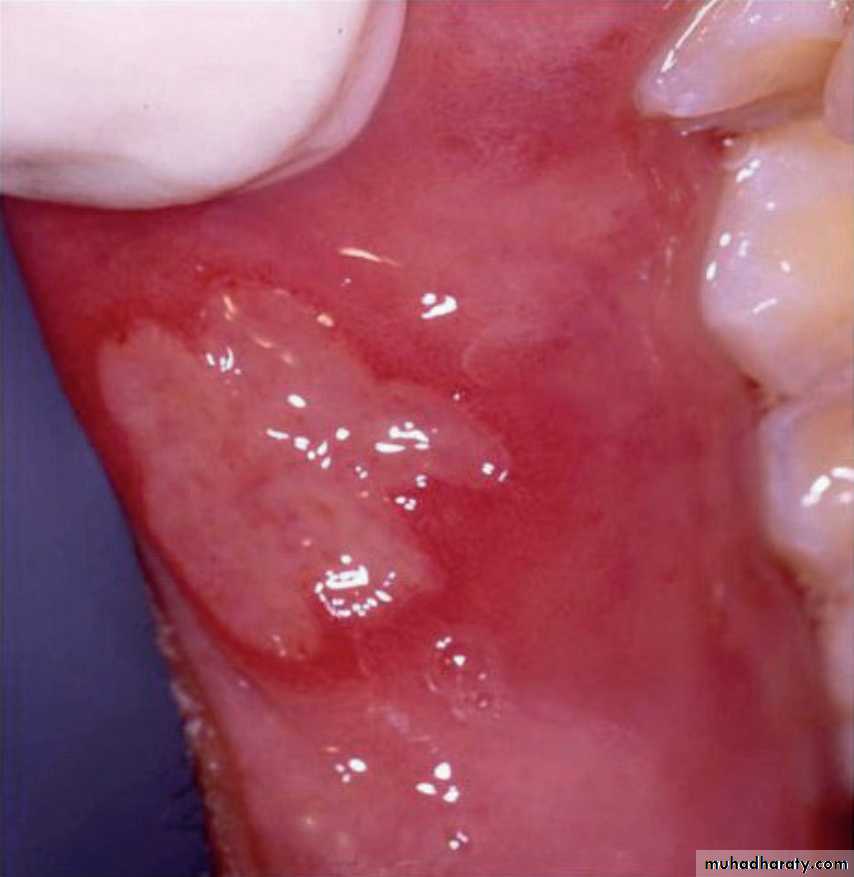

•Behçet’s disease/syndrome

Behçet’s disease/syndromeErythema nodosum. This is the commonest skin manifestation of Behçet’s disease.